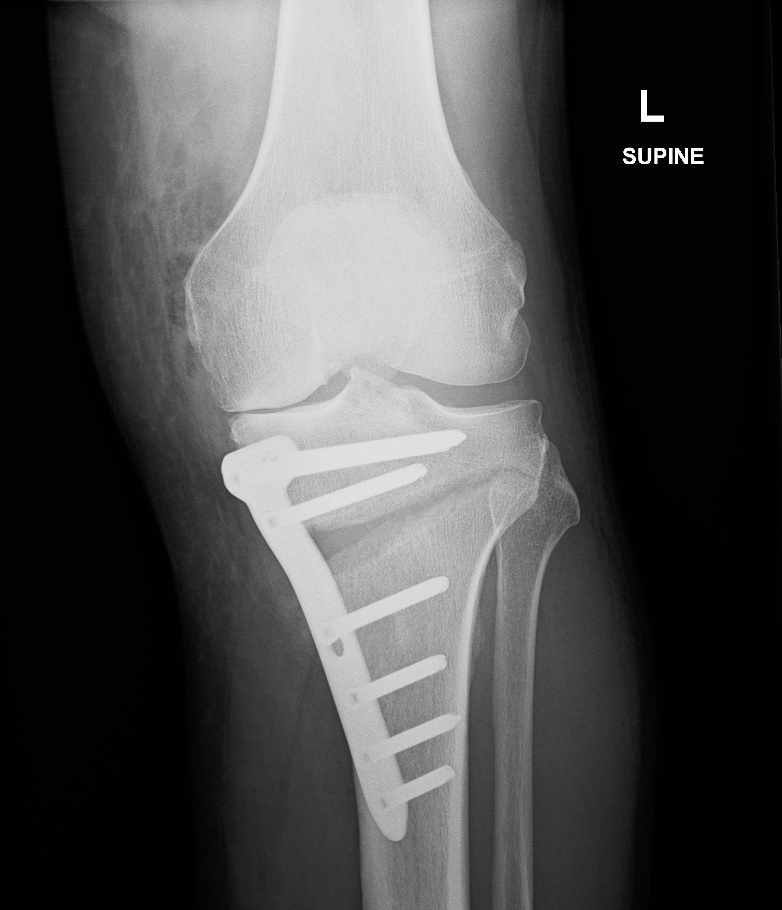

Example of High Tibial Osteotomy

A high tibial osteotomy,